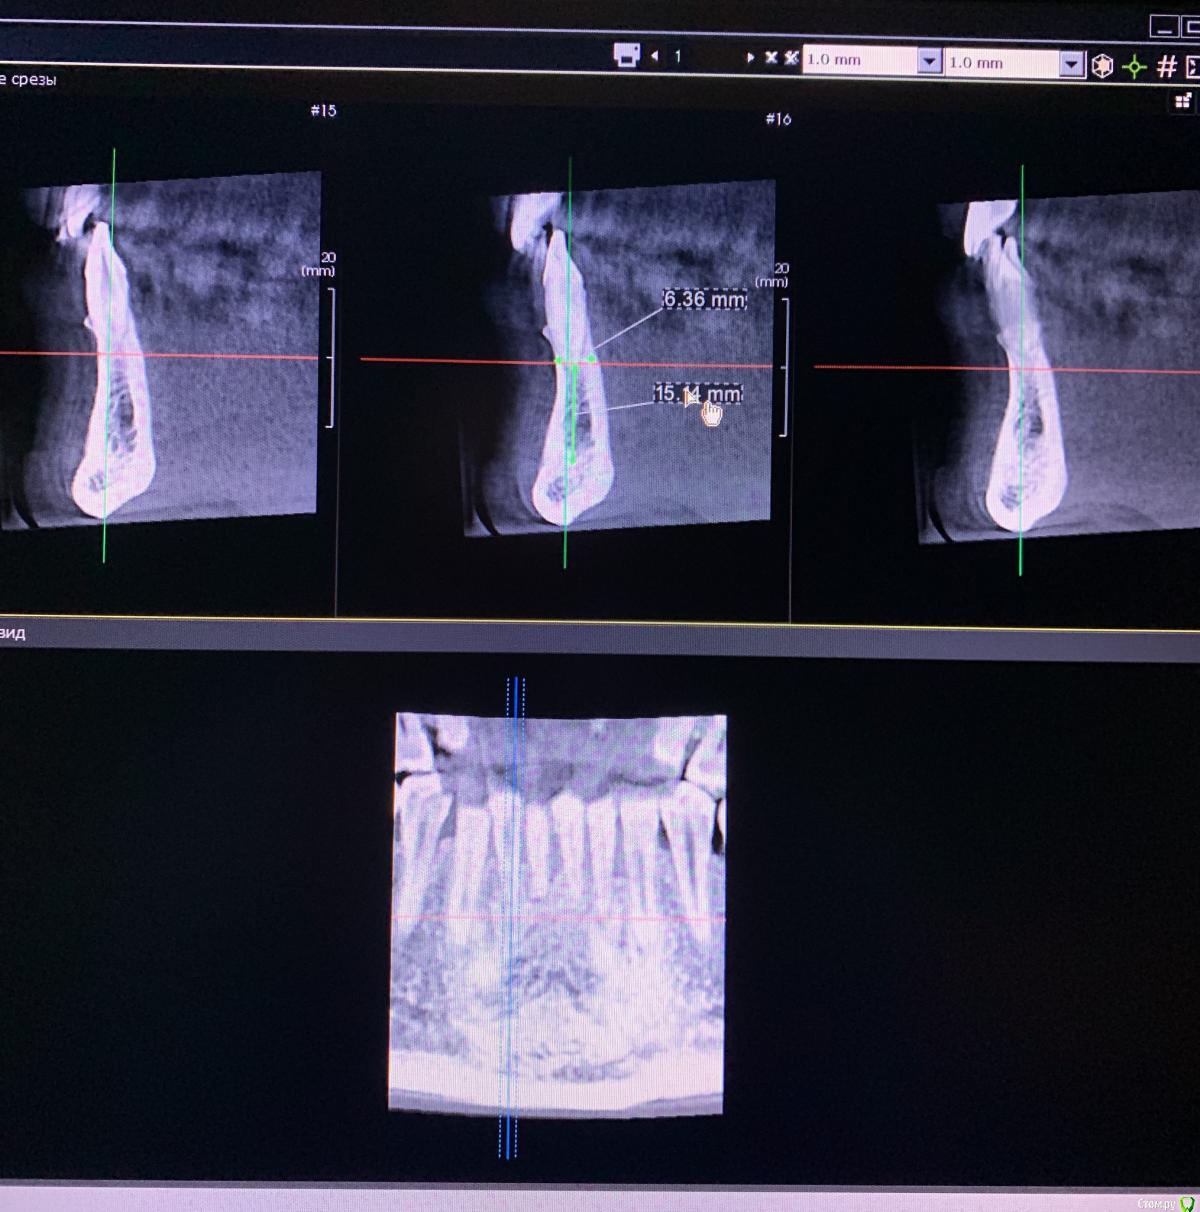

Opimar Опубликовано 17 декабря, 2019 Поделиться Опубликовано 17 декабря, 2019 Добрый день коллеги. Интересует ваше мнение по тактике лечения по данному клиническому случаю. Обратилась пациентка около 30 лет. с жалобами на подвижность нижних фронтальных зубов. Подвижность беспокоит давно. В полости рта скученность 42,41,31,32. Оголение корней 42/32 на треть, 41/31 на 1/2. Подвижность 42-32 1 степени, 41/31 1-2 степени. Слизистая оболочка не гиперемированна, не отечна, при пальпации отсутствуют выделения в области 42-32. На Кт ситуация на фото. Зубной ряд целостный за исключением 46, гигиена удовлетворительная, не курит. Имея опыт одномоментной имплантации, хочу предложить пациентки одномоментно удалить 42-32, установить 3.3 на 10/12 и нагрузить временным мостом. Что можете посоветовать? Одномоментно устанавливал в разных участках, но именно с фронтом на н.ч. впервые. Не хочу делать бабочку, боюсь еще больше атрофию получить. Костные условия есть и слизистая спокойная, думаю заглубить на 4-5 мм, Трансплантант добавить и в область 31-41.Заранее спасибо Ссылка на комментарий